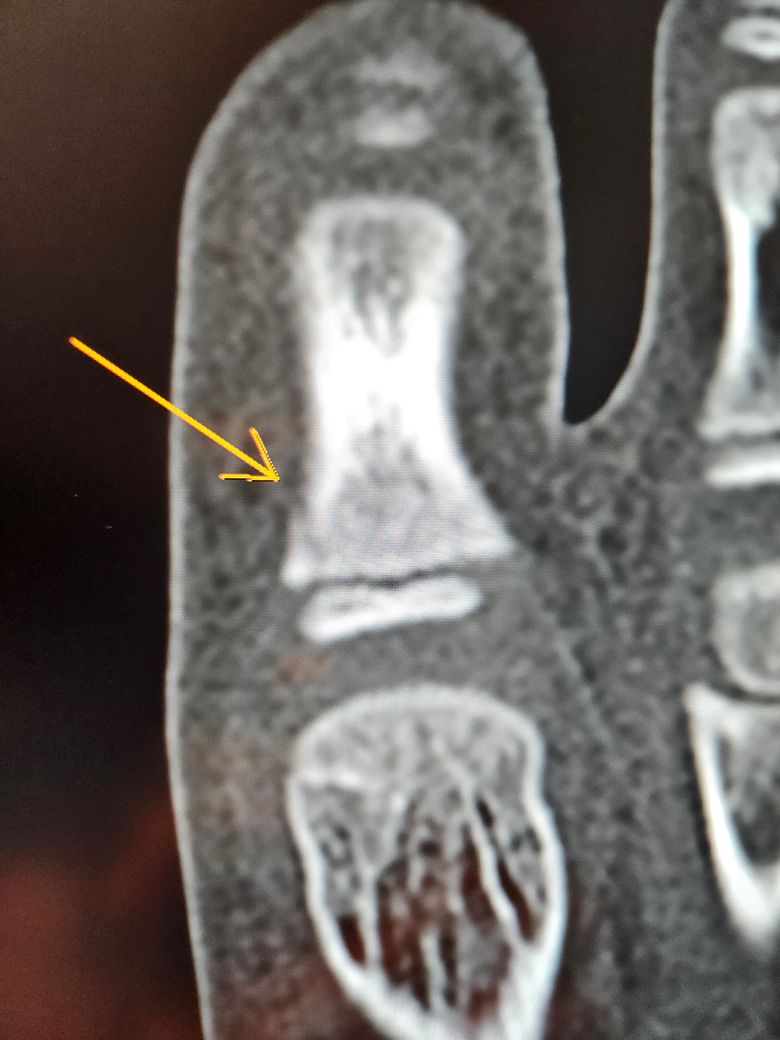

두번째 세번째는 ct입니다

수술하자하는데 제가 일주일만 경과보고프다해서 일단 통깁스만했는데ㅠ

핀 수술이 필요할까요?ㅠ